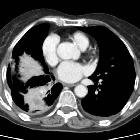

Epidermal growth factor receptor (EGFR) mutation can be expressed in a large proportion of non-small cell lung carcinomas (NSCLC). However, certain subtypes such as invasive mucinous adenocarcinoma of the lung can have very low expression.